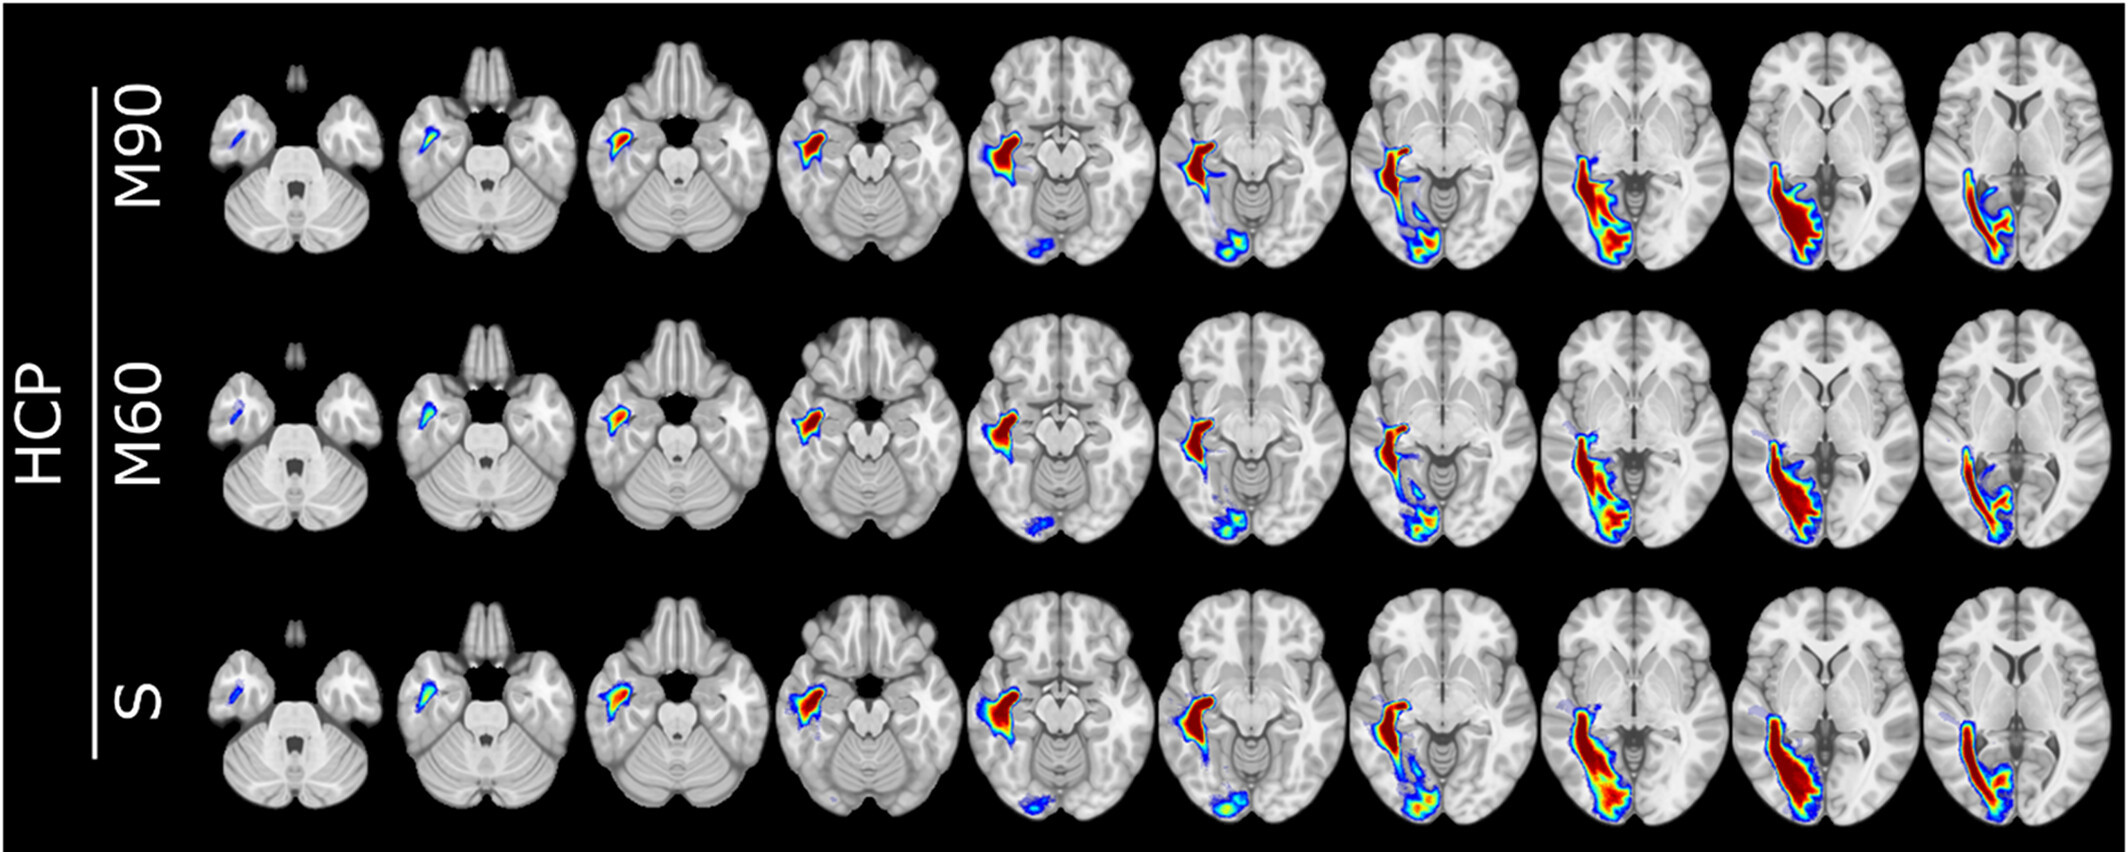

Fully automated delineation of the optic radiation for surgical planning using clinically feasible sequences

LB Reid, E Martínez-Heras, JV Manjón, RL Jeffree, H Alexander, et al. Human Brain Mapping

How many streamlines are required for reliable probabilistic tractography? Solutions for microstructural measurements and neurosurgical planning

LB Reid, MI Cespedes, K Pannek NeuroImage